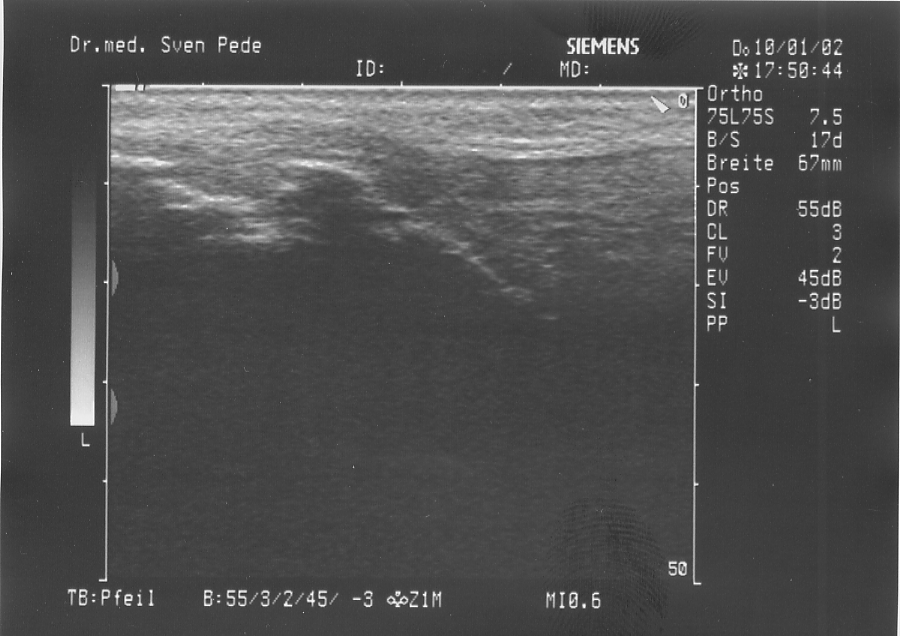

Morbus Osgood Schlatter

Bei dem Morbus Schlatter handelt es sich um eine Erkrankung, welche bei Jugendlichen im Alter zwischen 14 bis 16 Jahren abläuft. Es handelt sich um eine Verknöcherungsstörung des Ansatzbereiches der Kniescheibensehne am Schienbeinkopf. Der Ansatzbereich der Sehne verwächst nicht mit dem Schienbein, so daß hier ein isolierter Knochenkern bestehen bleibt.

Dies führt zu einer Verdickung, welche bei stärkerer sportlicher Belastung und insbesondere beim Knien schmerzhaft sein kann.

• Schlatter